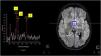

Papilledema was ruled out and the evaluation completed with head CT and MRI scans (Fig. 1). Based on the imaging findings, the principal diagnostic impression was diffuse midline glioma, although an inflammatory process could not be ruled out. This prompted extension of the evaluation with magnetic resonance spectroscopy (MRS), the findings of which were inconclusive for diagnosis of a tumor (Fig. 2). The surgical biopsy was deferred to perform a 11C-methionine PET scan, the findings of which were not suggestive of high grade glioma. Suspicion of autoimmune encephalitis prompted testing for anti-MOG/AQP4 antibodies (which turned out negative) and initiation of intravenous steroid therapy.1